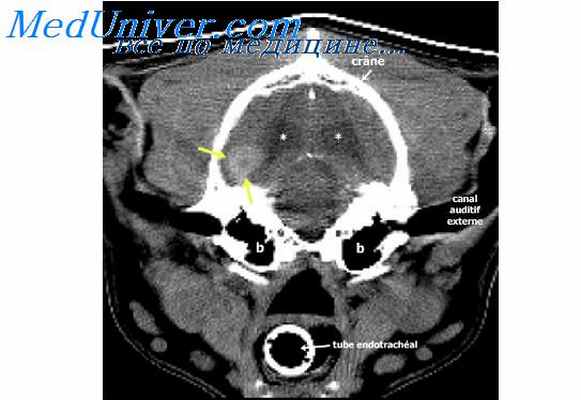

Компьютерная томография (КТ). Это исследование использует узкие рентгеновские лучи для получения подробного изображения поперечного сечения позвоночника. Иногда при этом вводят контрастное вещество для более отчетливого выявления патологических изменений в позвоночном канале или спинном мозге. Хотя исследование не является инвазивным, оно подвергает пациента большему воздействию радиации, чем обычный рентген.